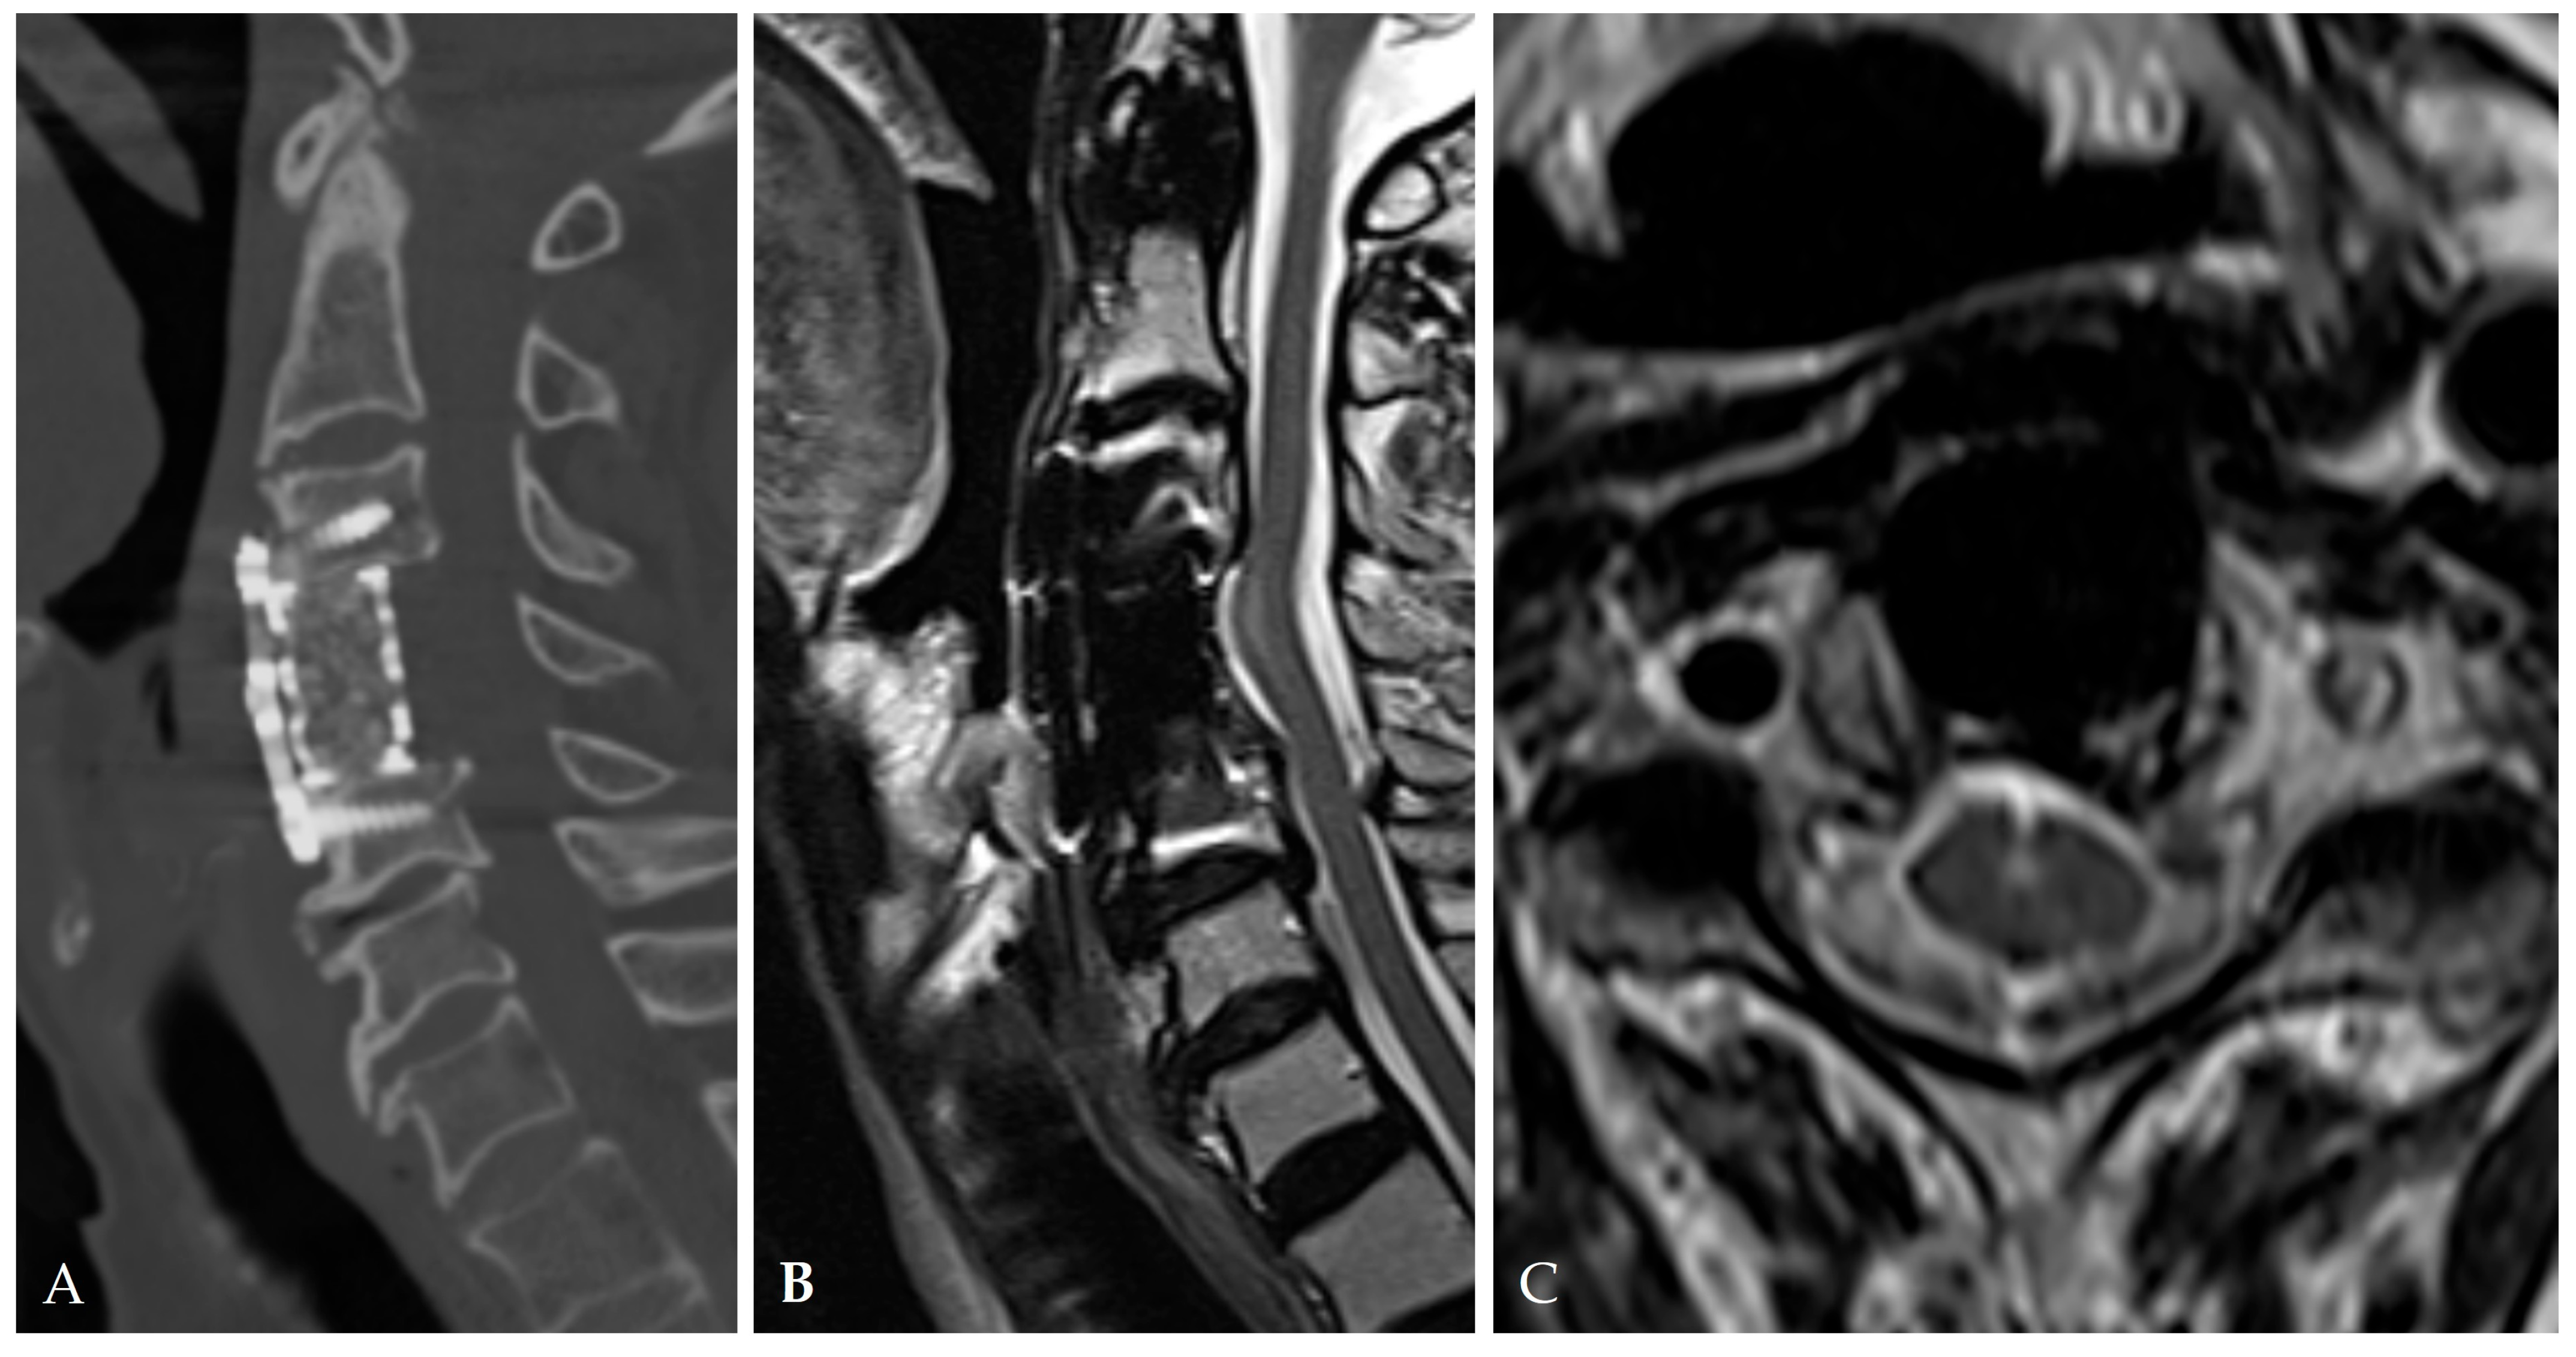

5. Postoperative Management and Outcomes

5.4. Pseudomeningocele Management

5.6. Functional Outcomes

6. Complications and Reoperation

6.3. Intracranial Hypotension and Remote Cerebral Hemorrhage

6.4. Mechanical/Implant-Related Complications

6.5. Pseudomeningocele and Late Recurrence

6.6. Reoperation Rates and Predictors

- Jang, S.W.; Lee, S.H.; Shin, H.K.; Jeon, S.R.; Roh, S.W.; Park, J.H. Management of CSF leakage by pump-regulated volumetric continuous lumbar drainage following anterior cervical decompression for OPLL. Neurospine 2023, 20, 1421–1430. [Google Scholar] [CrossRef]

- Moon, J.H.; Lee, S.; Chung, C.K.; Kim, C.H.; Heo, W. How to address cerebrospinal fluid leakage following ossification of the posterior longitudinal ligament surgery. J. Clin. Neurosci. 2017, 45, 172–179. [Google Scholar] [CrossRef]

- Kim, J.Y.; Oh, B.H.; Kim, I.S.; Hong, J.T.; Sung, J.H.; Lee, H.J. Safety and effectiveness of lumbar drainage for CSF leakage after spinal surgery. Neurochirurgie 2023, 69, 101501. [Google Scholar] [CrossRef] [PubMed]

- Elder, B.D.; Theodros, D.; Sankey, E.W.; Bydon, M.; Goodwin, C.R.; Wolinsky, J.P.; Sciubba, D.M.; Gokaslan, Z.L.; Bydon, A.; Witham, T.F. Management of CSF leakage during ACDF and its effect on fusion. World Neurosurg. 2016, 89, 636–640. [Google Scholar] [CrossRef]

- Yoshida, H.; Takai, K.; Taniguchi, M. Leakage detection on CT myelography for targeted epidural blood patch in spontaneous cerebrospinal fluid leaks: Calcified or ossified spinal lesions ventral to the thecal sac. J. Neurosurg. Spine 2014, 21, 432–441. [Google Scholar] [CrossRef]